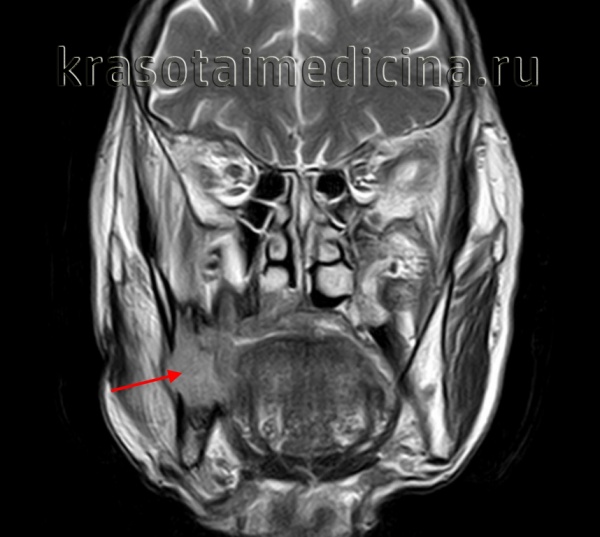

(Слева) На панорамной реформатированной КЛКТ у этого же пациента определяется резорбция корня зуба наряду с хорошо отграниченным рентгенонегативным образованием.

(Справа) На аксиальной КТ с КУ определяется деформация левой половины лица в результате предыдущей резекции амелобластомы, метастазирующей в мягкие ткани шеи и шейные позвонки. Злокачественная амелобластома в этом примере гистологически выглядит доброкачественной (отличной от амелобластического рака), но метастазирует в лимфоузлы и в отдаленные органы.